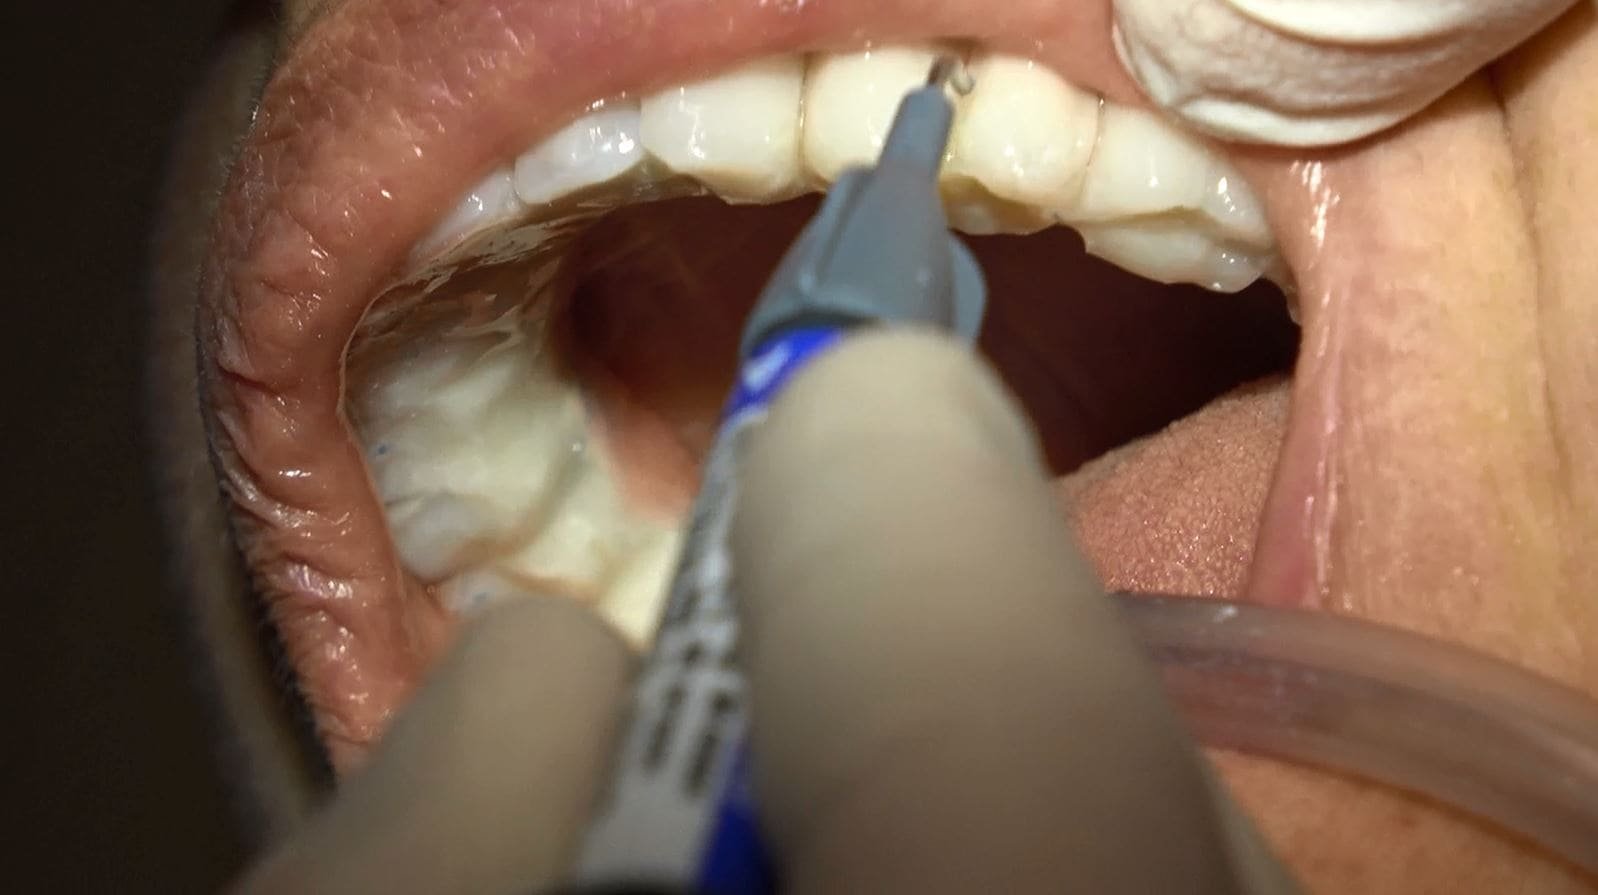

• Il video documenta ogni fase dell’intervento, dalla progettazione personalizzata della griglia sottoperiostea all’applicazione dei singoli impianti e, infine, alla realizzazione di una protesi dentale a carico immediato.

• Accompagniamo il video con una galleria fotografica dettagliata che cattura ogni fase del processo e i risultati finali sorprendenti.

• Dopo l’intervento, sarai monitorato attentamente per garantire una corretta guarigione e adattamento alla protesi provvisoria.

• Dopo un periodo di circa 6 mesi, quando l’integrazione degli impianti è completa, la protesi provvisoria può essere sostituita con una protesi dentale fissa definitiva in ceramica, composta da 14 denti.